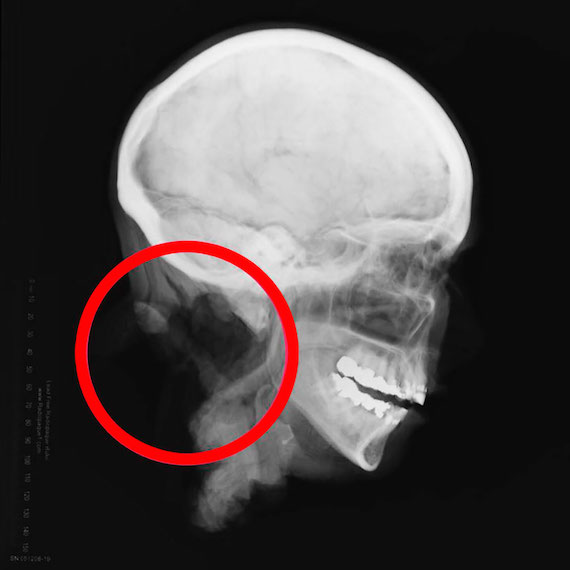

Разрез, который отделил ее голову от ненайденого тела, был очень точным и ровным, а оставшаяся часть позвоночника из шейного отдела была тщательно удалена.

При изучении глаз возникло еще больше загадок, так как самих глазных яблок найдено не было, вместо них были тонкие глазные линзы (их используют в моргах) а под ними красные резиновые шарики. Возникла версия, что глаза были удалены в донорских целях, но для этого обычно используют лишь роговицу и заменять глаза полностью красными шариками точно не распространенная процедура. Местный врач никогда не видел ничего подобного.

В итоге исследователи пришли к очень зловещему предположению. Если голову женщины отделили от тела с хирургической точностью и с помощью не ножей, а хирургических инструментов, вырезали ей глаза, забальзамировали ее, тщательно удалили части позвоночника и при этом все это не прошло ни через морги, ни через больницы, то это было сделано подпольно. Это хорошо развитая и скрытая сеть по торговле частями тел.